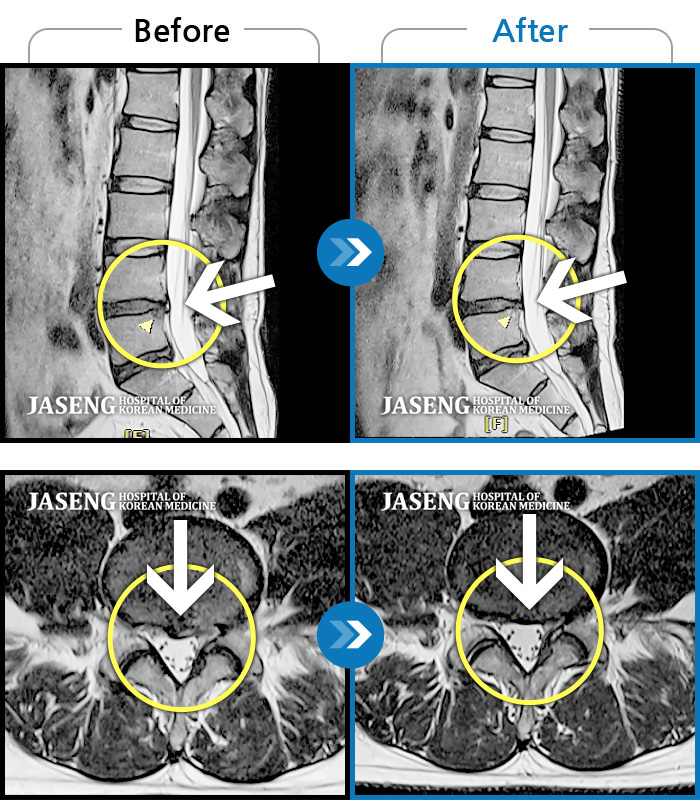

허리에 갑작스럽게 고통스러운 통증으로 내원해서 디스크라는 병명에 놀랐고 무서웠는데 따뜻하고 친절한 진료로 일단 마음이 안정이 되었고 무엇보다 수술없이도 치료가능 할꺼라는 말씀에 위안이 되면서 이선생님만 믿고 치료를 받으면 난 살겠다 라는 마음을 갖게 되며 입원치료를 받기 시작합니다. 침맞는 두려웅, 허리통증으로 유별나게 겁이 많은 나였지만 불편한내색 한번 없이 치료를 해주시고 안정을 주시니 말을 안해도 느껴지는 따뜻한 의료진이 내 주치의인게 너무 감사할따름이였습니다. 하루하루 치료과정에 상태도 꼼꼼히 체크해주시고 정말 거즘 기여서 병원을 들어와서 두발로 씩씩하게 퇴원을 하게 도와주신 장영우원장님 진심으로 감사드리고 자생한방병원에 따뜻한 의료진이 있어 안심이 됩니다

광주허리디스크로 고생하다가. 지인의소개로 장영우 원장님께 치료을 받았는데. 1년반판에 좋아졌는데 허리 3번4번이 또 터져서. 지금입원중인데. 많이 좋아지고 있어요 젊은 의사선생님이 친절하시고. 침도 진짜. 자놓읍니다. 잘생기신분이. 치료도 잘하시고. 믿음이 갑니다 정말감사드려요. 아무리 피곤하시고. 힘들어도 항상 웃는얼굴이 좋아요 감사합니다. 광주자생병원 장영우 원장님. 많이 칭찬합니다~~

살짝만 움직여도 허리가 끔벅거리고 아프고 일어나거나 눕지도 잘 못하고 걸음도 제대로 못걷고 옷도 못입을정도로 통증에 시달렸읍니다. 입원첫날 원장님한테 침맞고 통증이 좀 가라앉았어요 MRI 찍어보니 왼쪽디스크는 터졌고 6번은 터지기 직전 3 4 번은 부어있고 12번 1번은 심각한상태구요 몇일 통증치료하며 끔벅거리는게 없어 살겠더군요 종아리 발바닥 발등이 저려 무척힘들었는데 치료받으며 저린것도 허리아픈것도 많이 좋아졌어요 자금은 걷는것도 훨씬가벼워 졌어요 40대 후반 나이로 내가 벌써 이렇게 몸을 못쓸정도로 아프나 싶어 암담했었는데.. 치료받으며 좋아지니 마음도 훨씬 가볍네요 늘 친절한 모습으로 그날그날 상태를 살펴보며 정성껏 치료해 주시는 원장님 넘~~ 감사합니다!! 우리 원장님??????